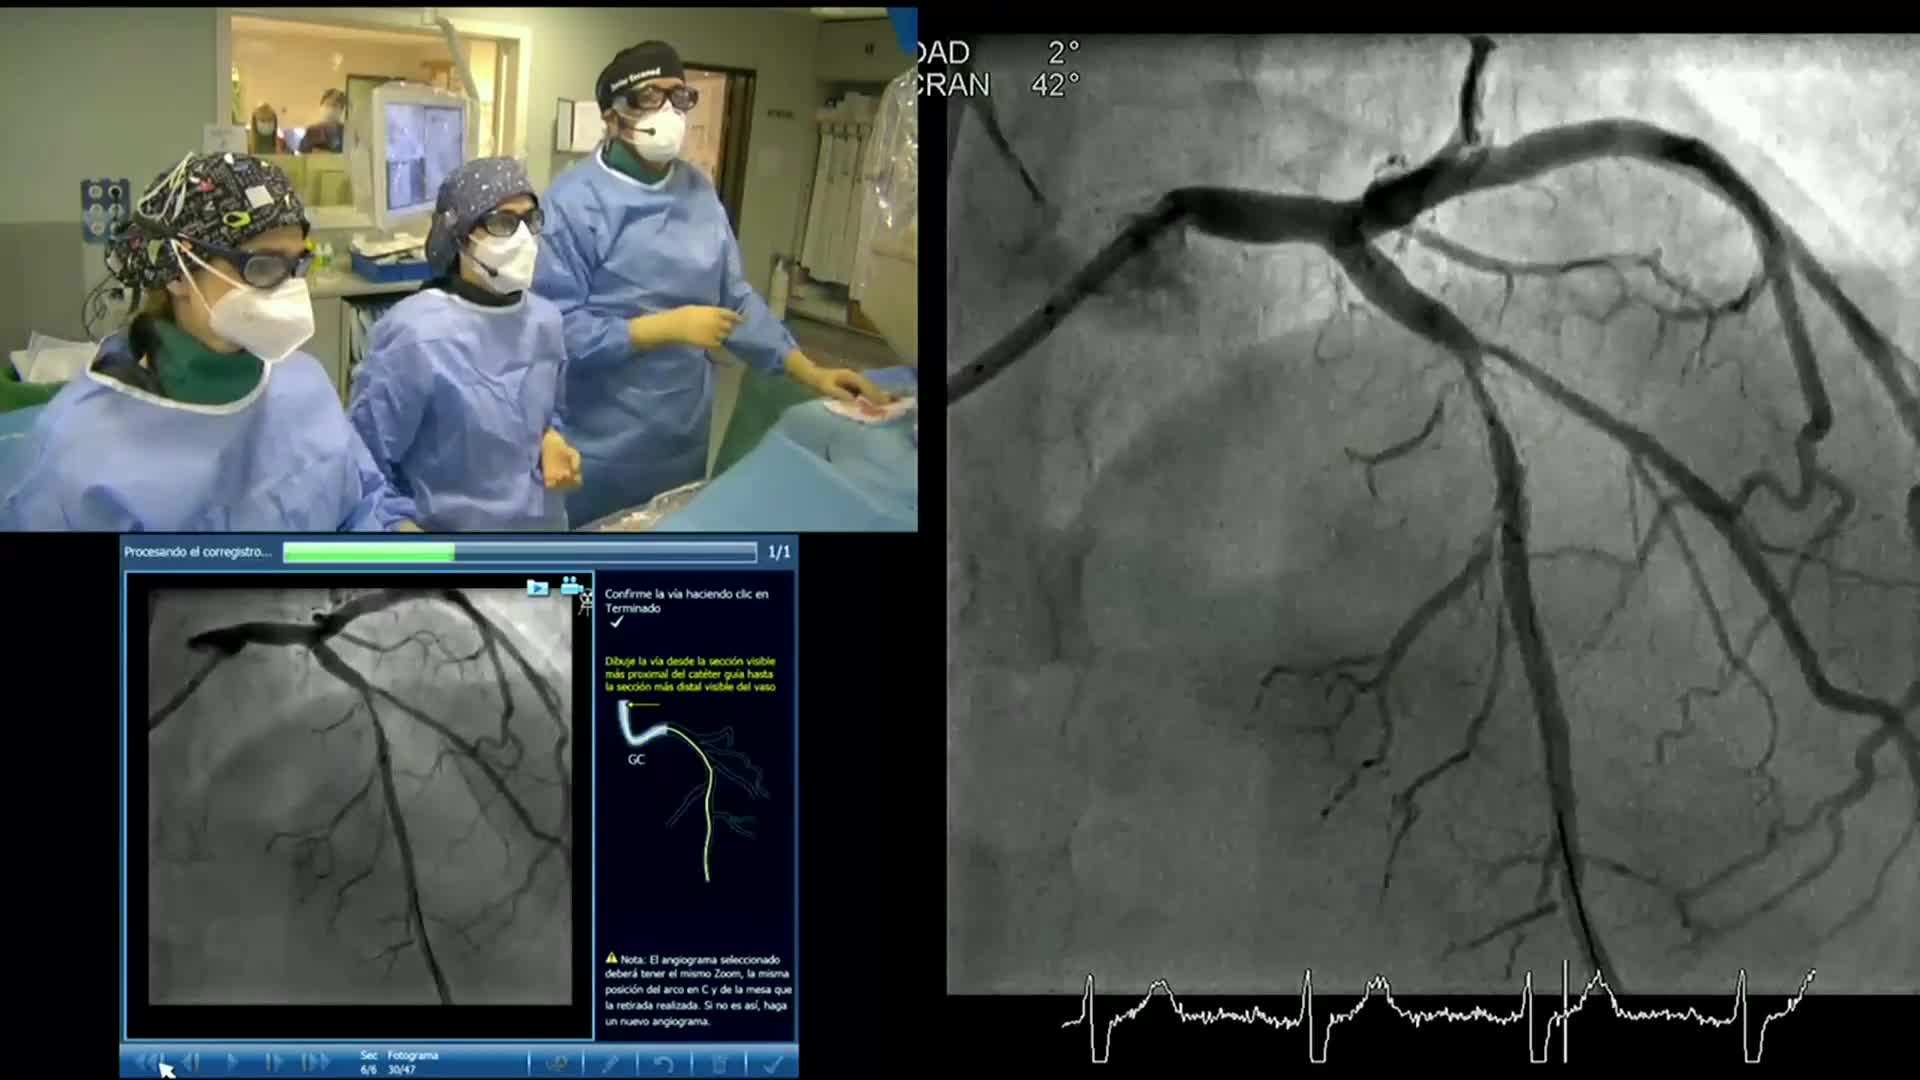

Co-registration eCourse October 2020 Day One

Co-registration eCourse October 2020 Day Two

Co-Registration Course Content

Understanding how SyncVision differs from other co-registration based technologies - Dr Justin Davies

How to perform good co-registration measurements using iFR and IVUS - Prof Carlo Di Mario

Using SyncVision Co-registration to distinguish between focal and diffuse coronary disease. - Prof Giuseppe Tarantini